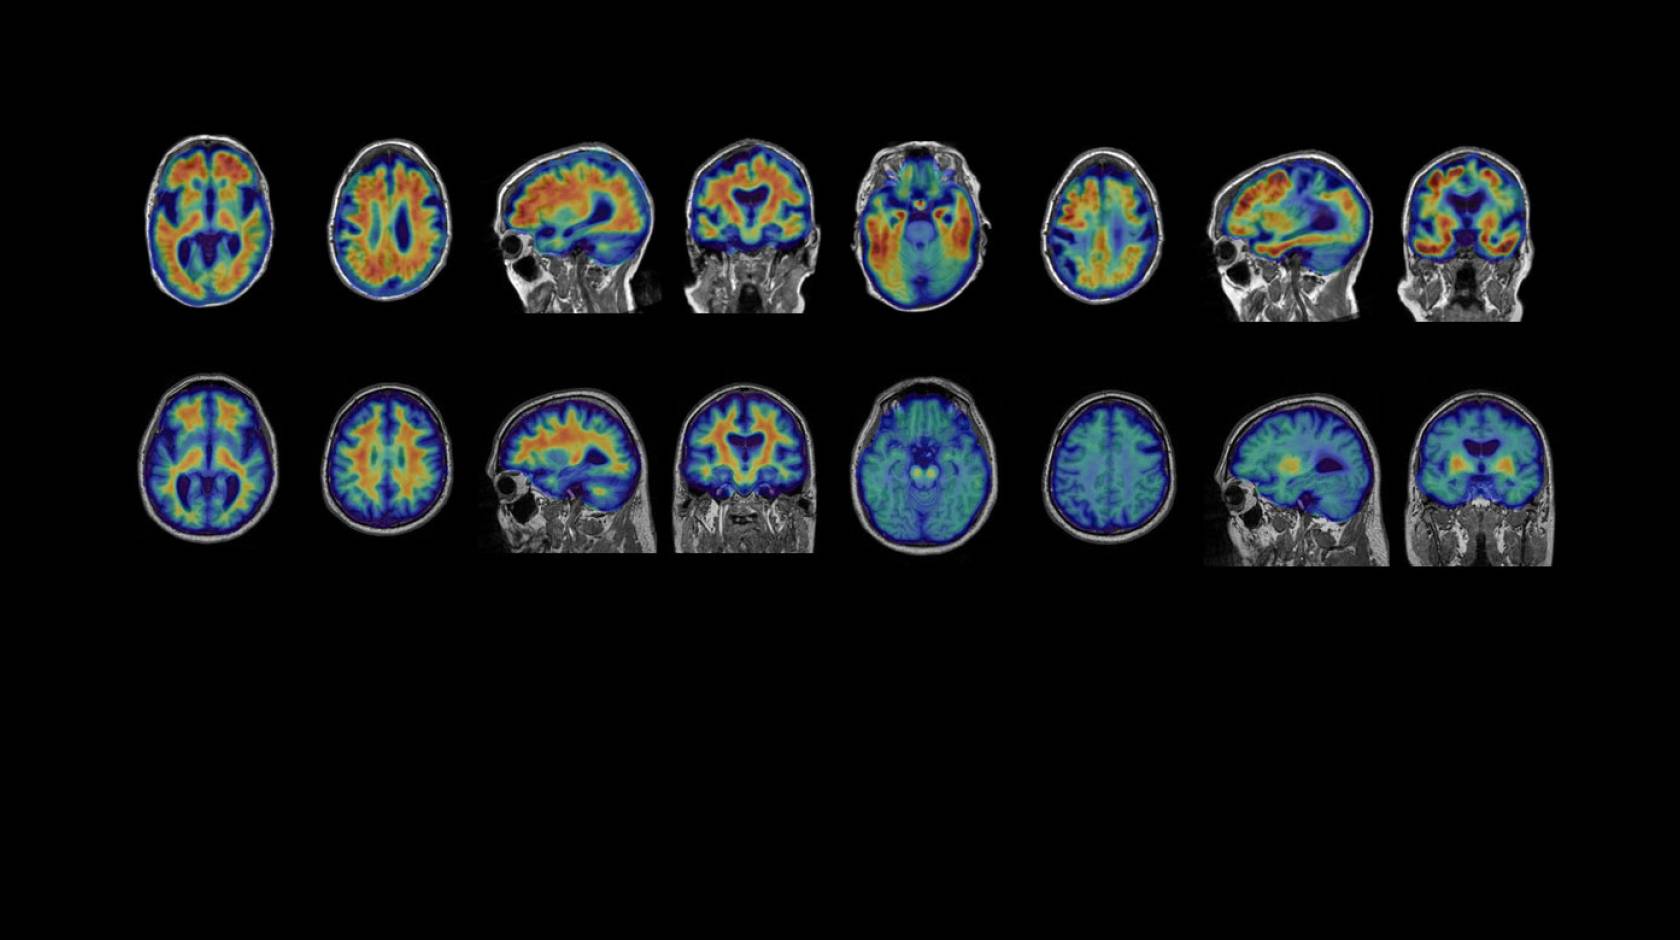

Gil Rabinovici, MD: One potentially serious adverse effect is amyloid-related imaging abnormalities (ARIA), which occur in patients treated with anti-amyloid therapies. This refers to swelling or microscopic bleeds in the brain. ARIA will need to be monitored closely with serial MRI, especially as patients initiate treatment. However, in the lecanemab trial, it was asymptomatic in 80% and very rarely associated with serious symptoms. The swelling typically resolves spontaneously and most patients can resume treatment. A genetic test will likely be recommended, since some variants of APOE, a gene that increases the risk of Alzheimer’s, are associated with a higher risk of ARIA.